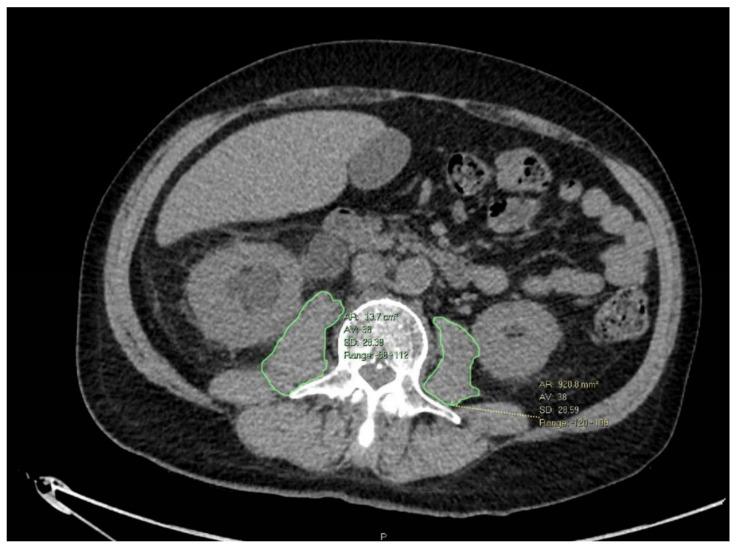

MATERIALS AND METHODS

We included MIBC patients who underwent RC and received NAC from multiple academic centers in Israel. Cross-sectional imaging was used to measure the psoas muscle area and normalized it by height (smooth muscle index, SMI). Pre- and post-NAC SMI difference was calculated (represents nutritional status change). The primary outcomes were post-RC ileus, infection, and a composite outcome of any complication. Logistic regression models were fit to identify independent predictors of the outcomes.

我们纳入了在以色列多个学术中心接受 RC 并接受 NAC 的 MIBC 患者。采用横断面影像学测量竖脊肌面积,并通过身高进行归一化(平滑肌肉指数,SMI)。计算 NAC 前后 SMI 的差异(代表营养状况的变化)。主要结局为 RC 后肠梗阻、感染和任何并发症的综合结局。采用逻辑回归模型确定结局的独立预测因素。